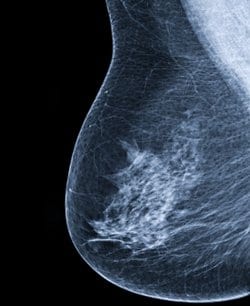

מגמות הטיפול בסרטן השד בשלבים מוקדמים

שיעורי כריתות השד, כריתות השד הדו צדדיות ושחזורי השד מצויים בעלייה.

החולות בארה”ב נוטות לבקש כריתה בתדירות רבה יותר מ- (breast-conserving surgery (BCS.

על מנת לבדוק את מגמות הביצוע של כריתה או BCS נעזרו החוקרים במידע מה- National Cancer Data Base וערכו מחקר קוהורט רטרוספקטיבי שכלל מעל ל- 1.2 מיליון המתאימות ל- BCS עם סרטן שד המצוי בשלבים מוקדמים (T0-2, N0-2, ו- M0) ואשר טופלו בין השנים 1998-2011.